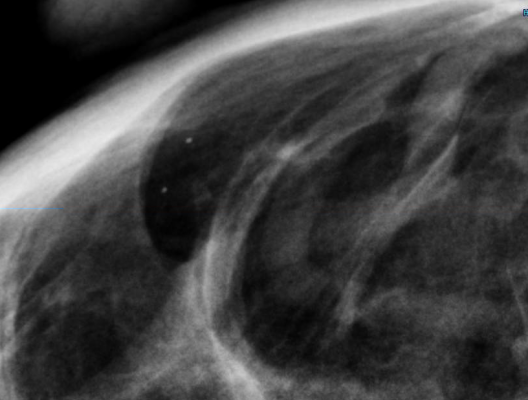

CureMetrix is currently developing a physics-based software algorithm that allows radiologists to get more specific and sensitive readings of breast images from existing imaging systems.

CureMetrix was founded in 2014 on the belief that better medical image analysis technology could lead to better outcomes for breast cancer patients. The company is developing investigational physics-based artificial intelligence and deep machine learning solutions to help radiologists get more accurate readings of breast images. Through its research partnerships with leading hospital radiology departments, CureMetrix has evaluated more than 500,000 mammogram images to identify potential false negatives, which are undiagnosed cancers, and false positives, which are unnecessary recalls of patients to review anomalies that turn out to be normal. False negatives can occur at a rate of about one in five breast cancers.1 False positives affect 7-12 percent of all women after an initial mammogram.2 Reducing false positives could save a significant portion of the $4 billion per year spent on unneeded and sometimes invasive procedures such as biopsies.3 More importantly, reducing false negatives could save lives as well as reduce the cost and difficulty of cancer treatment through early detection.